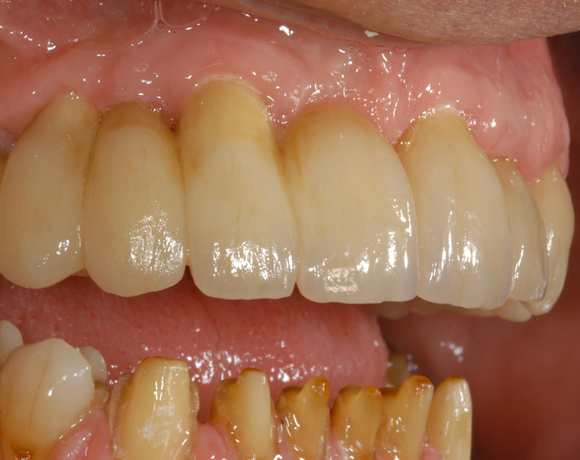

6 Implantate und viele Kronen und Brücken

Mit dem zweiteiligen vollkeramischen Implantat lassen sich auch große Lücken überbrücken.

Im vorliegenden Patientenfall waren die Zähne 11 – 26 mit einer provisorischen Brücke versorgt, der Patient konnte damit aber nicht essen. Auch im Unterkiefer waren die vorhandenen Kronen und Brücken insuffizient. Es wurde eine komplette Neuversorgung für Ober- wie Unterkiefer geplant.